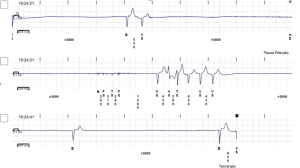

La cardioneuroablazione è indicata per i pazienti che soffrono di bradicardia (battito cardiaco lento) sintomatica per fatica e incapacità di svolgere le attività quotidiane. È particolarmente utile per coloro che hanno episodi di svenimenti (sincope) legati a un eccesso di tono vagale, con induzione di pause asistoliche prolungate (come nell’ esempiodella figura 1) e che dovrebbero impiantare un pacemaker come trattamento alternativo. Questa metodica alternattiva è particolarmente efficace nei pazienti più giovani, evitando al contempo i rischi a lungo dertmine di un impianto di pacemaker.

Figura 1